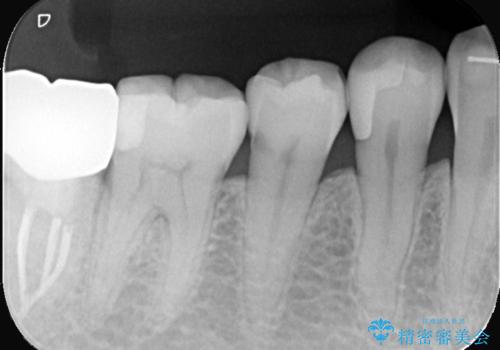

セラミックインレーによる虫歯治療

- 右下5の虫歯をセラミックインレーで修復しました。虫歯は進行することで歯に悪影響を及ぼし、放置するとさらなる問題を引き起こす可能性があります。再発のリスクをできるだけ回避するため、セラミックインレーを用いて治療を行いました。

装着する際にはラバーダムを使用しています。